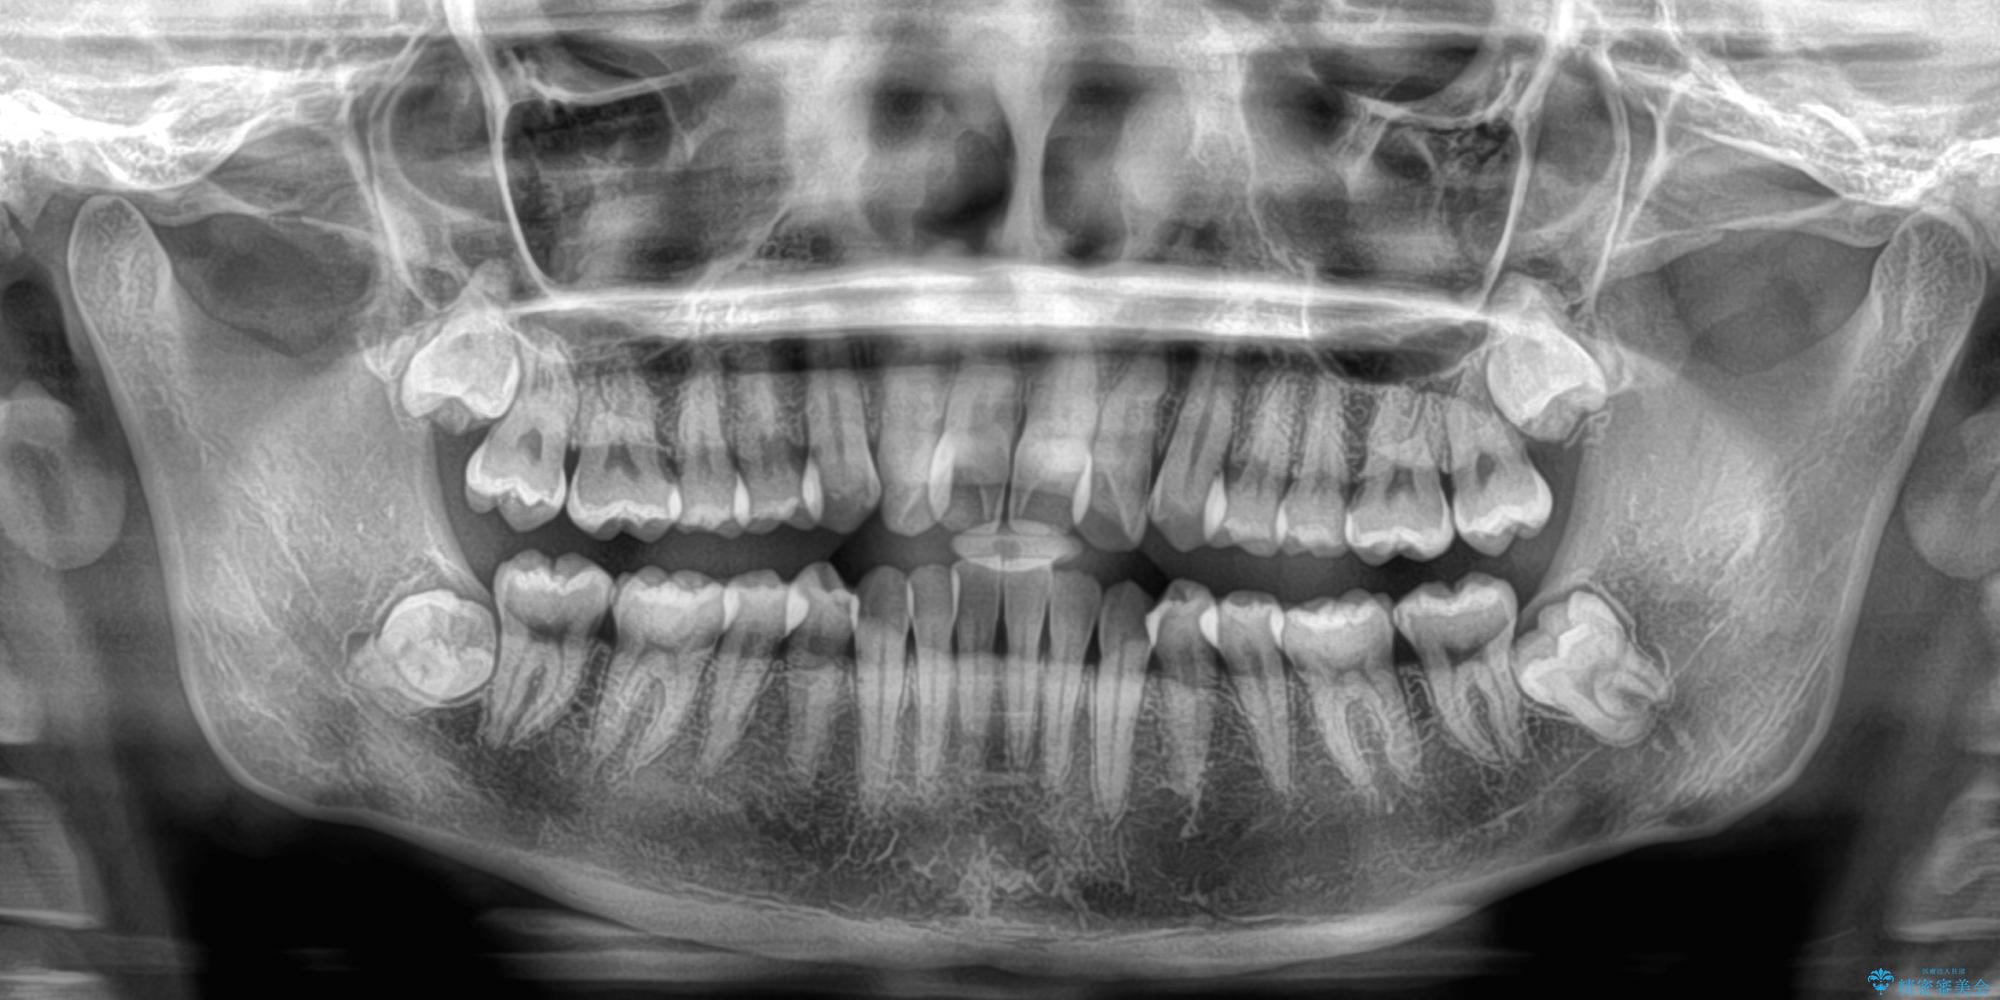

- 上顎前歯のクロスバイトを気にして来院された患者様です。

ワイヤー矯正でもマウスピース矯正でも対応可能でしたが、マウスピースによる自己管理に一切の自信がないとのことで、ワイヤー装置にて矯正治療を行うこととしました。